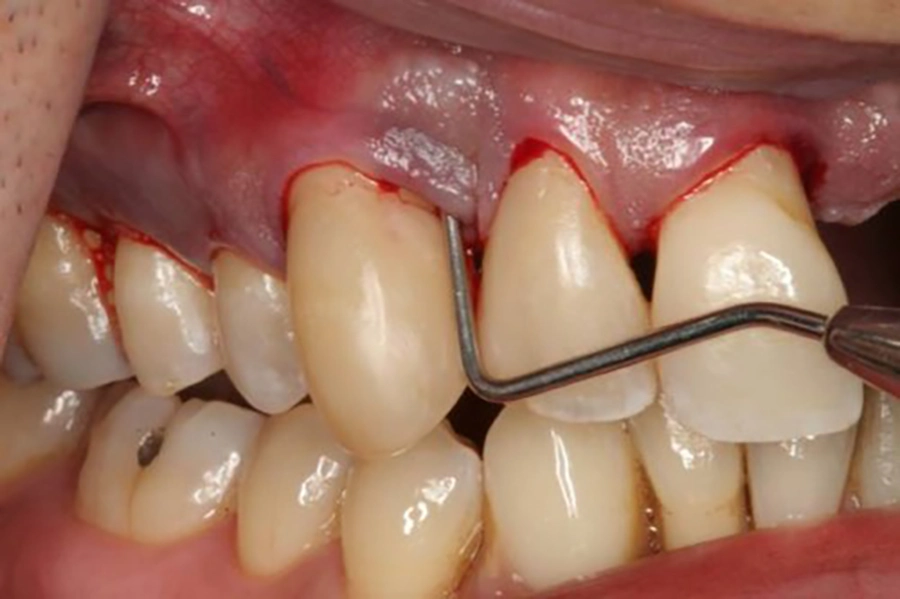

2.1 Nướu sưng đỏ và chảy máu bất thường

Một trong những dấu hiệu sớm nhất của bệnh nha chu chính là nướu bị viêm, sưng to và đổi sang màu đỏ sẫm thay vì hồng nhạt như bình thường. Người bệnh dễ dàng nhận thấy nướu bị mềm, dễ tổn thương và chảy máu ngay cả khi chải răng nhẹ hoặc ăn các thức ăn cứng. Đây là hiện tượng nhiều người thường bỏ qua, nghĩ rằng chỉ là viêm nướu nhẹ, nhưng thực tế lại là bước khởi đầu của bệnh nha chu.

Khi nướu đã viêm, các mạch máu bên trong bị giãn nở và thành mạch yếu đi, khiến việc chảy máu xảy ra thường xuyên hơn. Nếu không được xử lý kịp thời, tình trạng này sẽ ngày càng nặng, nướu không còn đủ sức nâng đỡ răng, tạo điều kiện cho vi khuẩn tấn công sâu hơn vào các mô bên dưới.

Bước đầu tiên trong quy trình chẩn đoán là bác sĩ sẽ thăm khám trực tiếp tình trạng nướu và răng. Bằng mắt thường và dụng cụ chuyên dụng, bác sĩ kiểm tra mức độ viêm, tình trạng sưng đỏ, chảy máu và độ sâu của túi nha chu.

Khám lâm sàng giúp phát hiện sớm những bất thường mà người bệnh có thể bỏ qua trong sinh hoạt hàng ngày. Đây cũng là bước quan trọng để phân biệt viêm nướu đơn thuần với viêm nha chu đã tiến triển. Từ đó, bác sĩ sẽ quyết định cần làm thêm các xét nghiệm hay chụp phim để có chẩn đoán chính xác hơn.